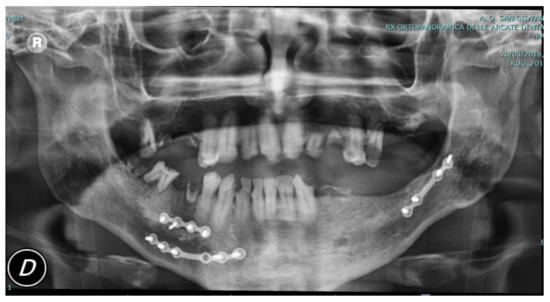

In the following figures, the medical images, orthopanoramic images (Figure 6 and Figure 7) before and after an orthognathic surgery, the implanting screws (Figure 8), and a digital reconstruction (Figure 9) are shown.

Figure 6. Pre-operative view showing fixation plates following jaw fracture care after the patient’s car accident.